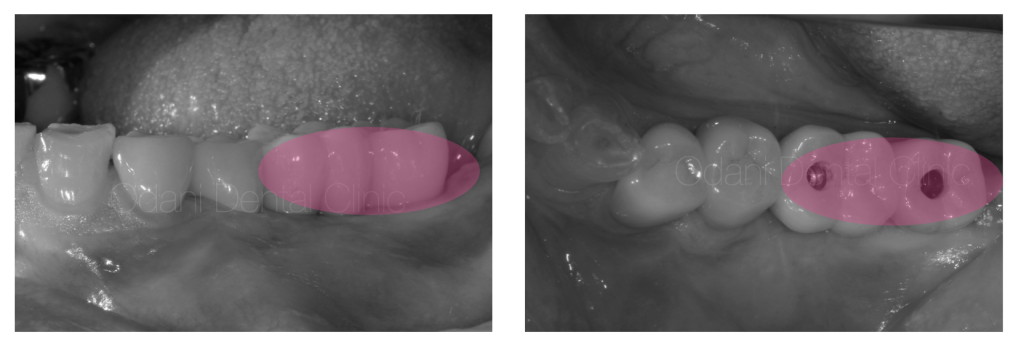

事前のCT画像によるシミュレーション通り、インプラント体を埋入するとインプラントのネジが大きく露出した状態(左写真)です。骨を作りたいところにチタン性のピンをテントの支柱のようなイメージで植立し、骨移植材を用いて骨造成を図りました(右写真)。

一次手術治癒後の状態です。骨造成を図ったことで、もともとの歯ぐきのヘコみが改善しました。

ピンク印:治療した部位